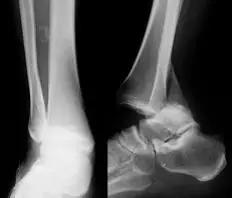

5. Maisonneuve 骨折

腓骨近端骨折伴内踝骨折及三角韧带断裂。

(来源:Radiopaedia)